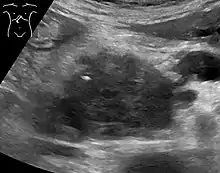

Medical imaging techniques, such as computed tomography (CT scan) and endoscopic ultrasound (EUS) are used both to confirm the diagnosis and to help decide whether the tumor can be surgically removed (its "resectability").[12] On contrast CT scan, pancreatic cancer typically shows a gradually increasing radiocontrast uptake, rather than a fast washout as seen in a normal pancreas or a delayed washout as seen in chronic pancreatitis.[51] Magnetic resonance imaging and positron emission tomography may also be used,[2] and magnetic resonance cholangiopancreatography may be useful in some cases.[29] Abdominal ultrasound is less sensitive and will miss small tumors, but can identify cancers that have spread to the liver and build-up of fluid in the peritoneal cavity (ascites).[12] It may be used for a quick and cheap first examination before other techniques.[52]